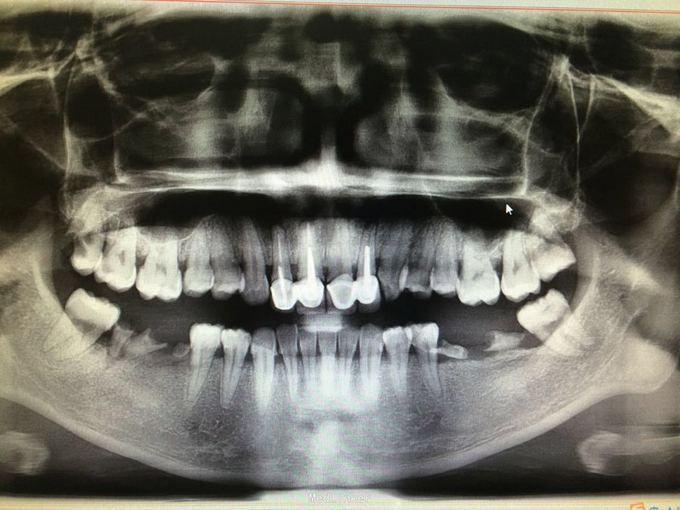

11 12 21 22金属烤瓷冠修复,牙龈发黑,冠颈部牙龈萎缩红肿有黑褐色腐质物,探出血,叩(-).23近中颊侧扭转倾斜.36 37 46 47残根,松动轻,全口牙结石中度,牙齿颜色偏黄,全景片示,11 12 21 22根管治疗不完善,根尖低密度影,有金属桩修复

11 12 21 22死髓牙,不良修复体,牙龈炎 36 37 46 47残根 牙列不齐 处置:全口洁治。 比色,拍照,取模型做蜡型。 拆除旧修复体,拆桩核,做根管治疗,纤维桩修复,牙体预备,取模,做临时冠,粘固。11 12 21 22全瓷冠修复,13 14 23 24 31 32 33 34 41 42 43 44瓷贴面修复。